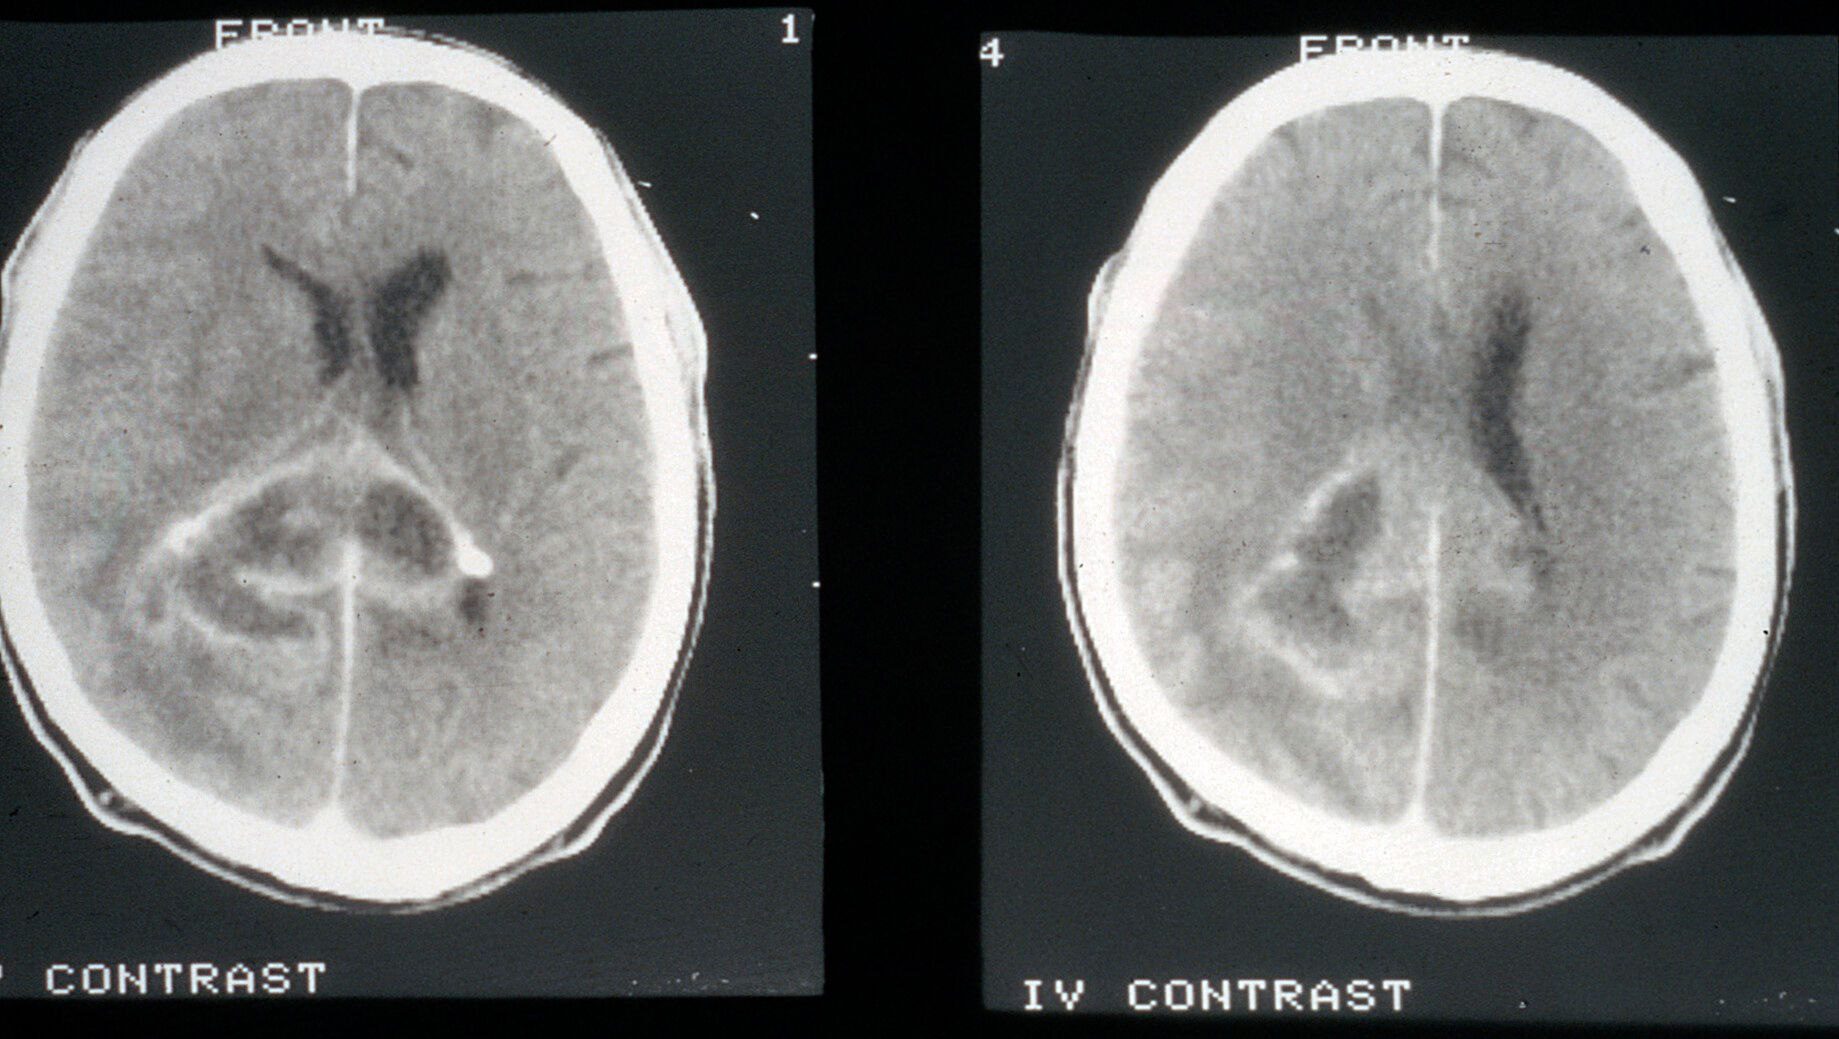

View Ct Brain Glioma Pictures. Glioma is a broad category of brain and spinal cord tumors that come from glial cells brain cells that support nerve cells. Terminology unless otherwise specified the term brainstem glioma usually refers to the most.

Mixed glioma involves both astrocytes and oligodendrocytes. There are multiple kinds of brain tumors. Gliomas are among the most common types of brain cancer. In ct glioma are hypodense, in mri hyperintense in t2 and hypointense in t1.